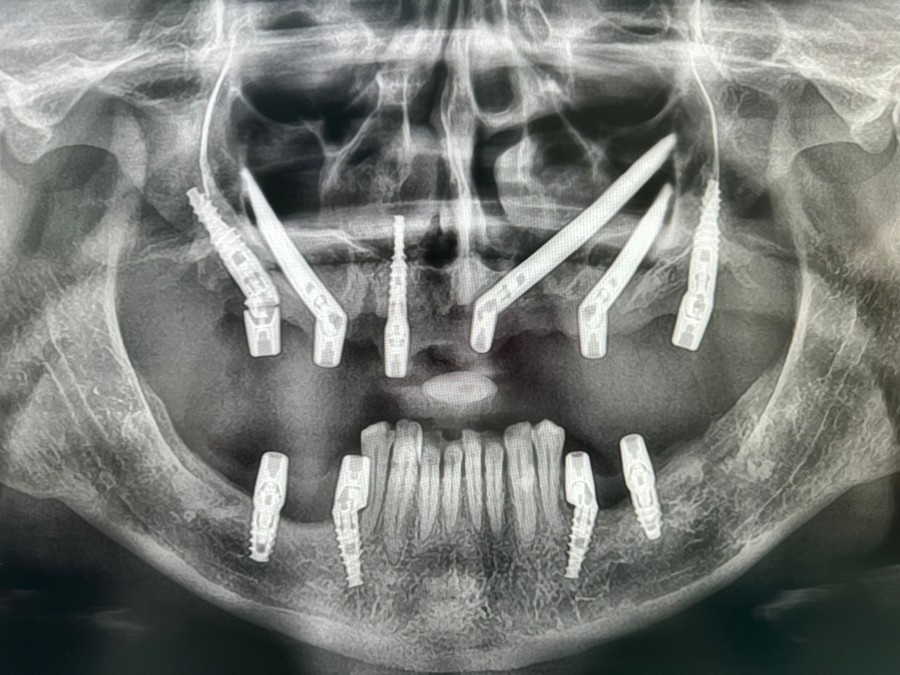

Impianti Zigomatici per Anziani

Impianti zigomatici vanno bene per gli anziani?

Gli impianti zigomatici sono una soluzione alternativa agli impianti dentali tradizionali per pazienti che hanno una...